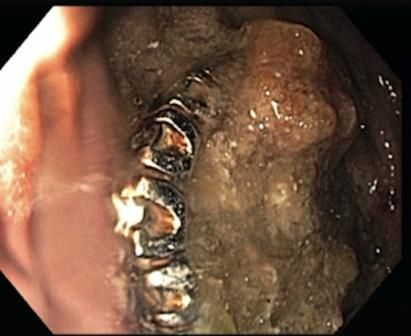

A 73-year-old man with a medical history significant for Parkinson dementia and esophageal adenocarcinoma with surgical resection and anastomosis at the gastroesophageal junction (GEJ) was admitted to the hospital following 3 weeks of progressive weakness, confusion, and decreased oral intake. Most of the patient’s symptoms were attributed to a urinary tract infection; however, a chest x-ray film revealed 3 peculiar ring-like structures within the stomach (Figure 1). The patient subsequently underwent an esophagogastroduodenoscopy (EGD) that revealed a large amount of food debris in the stomach in addition to what appeared to be a large diamond ring flanked by 2 gemstone-studded bands (Figure 2). En bloc retrieval of the entire treasure was initially attempted with a Roth® net; however, the size of the objects prohibited removal past the post-surgical anastomosis at the GEJ.

Figure 2